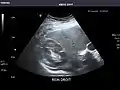

Liver